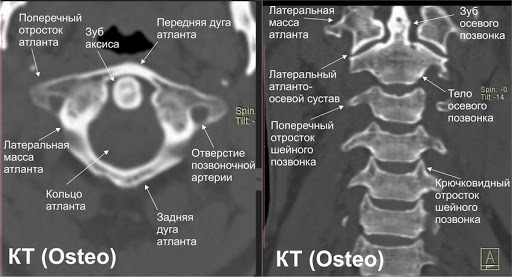

На этом снимке МРТ хорошо видно достаточно однородную структуру подкожного жира, формирующего холку. Никакие это не соли или какие бы то ни было другие минералы.